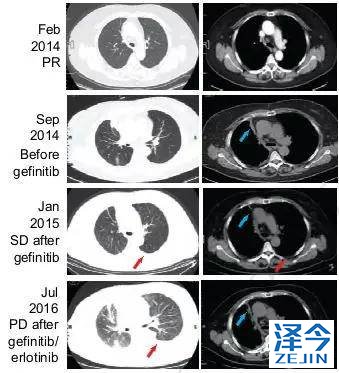

化疗,一代TKI治疗后,病情依旧进展

患者先进行化疗,基因检测显示为EGFR 19号外显子缺失,开始使用一代TKI药物治疗。一代TKI耐药后,发现患者出现T790M突变。

奥西替尼AZD9291治疗,病情稳定一段时间后,继续进展

因此,患者开始接受每日80mg的奥西替尼AZD9291治疗,患者在一个月内达到了病情稳定(SD),CA125水平迅速下降,经过8个月的无进展生存期,患者肺左下叶出现新的病灶,胸腔积液增多,病情发展。